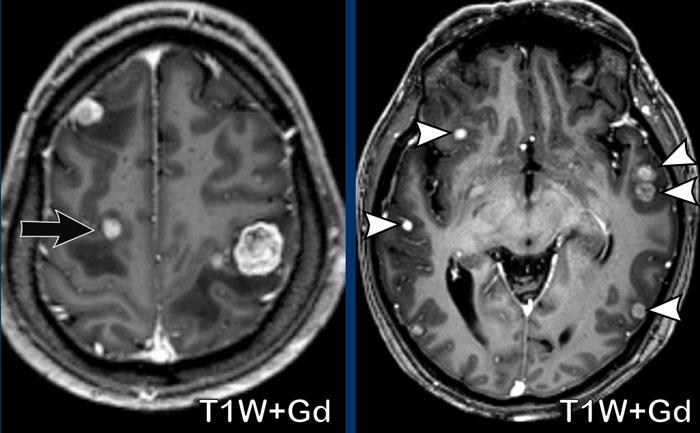

Di căn não

Hãy quan sát các hình ảnh trước rồi mới tiếp tục đọc.

Câu hỏi:

- Chẩn đoán có khả năng nhất là gì?

- Những dấu hiệu nào điển hình cho chẩn đoán này?

Các dấu hiệu bao gồm:

- Nhiều nốt nhỏ ngấm thuốc.

- Vị trí tại ranh giới chất xám/chất trắng và vùng phân thủy là rất điển hình cho di căn não, do các thuyên tắc khối u bị mắc kẹt tại những vùng có khẩu kính mạch máu rất nhỏ.

Trong 25-45% trường hợp, di căn não có thể là đơn độc.

Đây là một bệnh nhân khác với di căn não.

Một lần nữa, hãy chú ý vị trí tại vùng phân thủy (mũi tên đen) và tại ranh giới chất xám/chất trắng (đầu mũi tên trắng)